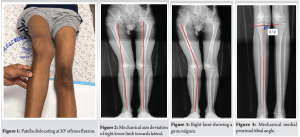

A 16-year-old boy presented to our outpatient department with a history of recurrent patellar dislocation in his right knee for the past 3 years. He also complained of a deformity of his right knee. On examination, his patella was grossly unstable, dislocating at about 30° of knee flexion (Fig. 1). Whole limb X-ray revealed a lateral mechanical axis deviation of 30 mm from the neutral (normal range – <10 mm) (Fig. 2). The opposite limb was normal. The Q angle of the right lower limb was measured to be 22°, which was abnormal (normal range 13–18°). The right knee was in valgus with a tibio-femoral angle of 15° (Fig. 3). The mechanical medial proximal tibial angle was 87.8° which was normal (normal range 85–90). However, the mechanical lateral distal femoral angle was 81°, which was abnormal (normal range 85–90) (Fig. 4 and 5). Hence, it was the distal femur that contributed to the genu valgum. The tibial tubercle–trochlear groove distance was 17 mm, which was normal (normal – under 20 mm), signifying that there was no rotational deformity. The Insall-Salvati ratio was 1.2, which was also normal (range – 0.8–1.2). Magnetic resonance imaging (MRI) revealed a Dejour Type D trochlea dysplasia (Fig. 6) with a trochlear depth of 1.2 mm (normal >3 mm) and a sulcus angle of 172 (normal <140). MRI also revealed an MPFL tear. The factors contributing to the patellar instability were recognized as the unacceptable genu valgum, trochlear dysplasia, and the MPFL tear. Considering that the patient had attained skeletal maturity and to avoid multiple procedures, a decision was made to correct all the anatomical abnormalities as a single procedure.